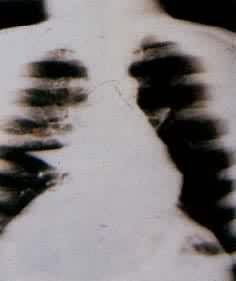

肺部肿瘤分为良性、恶性两大类。常见的恶性肿瘤为原发性支气管肺癌(简称肺癌)约占肺部肿瘤的90%。其次为肺转移性癌,多来源于泌尿生殖器官、胃肠、甲状腺、乳腺等。肺部良性肿瘤如错构瘤、脂肪瘤、乳头状瘤等较为少见。近年来肺癌的发病率、死亡率都有明显上升的趋势。在发达的国家,男性常见恶性肿瘤中肺癌已占首位,女性常见恶性肿瘤中占第二、三位。肺癌病因尚未明确,但已知其发病与长期吸烟、大气污染、接触某些理化致癌物质(如煤焦油,沥青,石棉,放射性铀、镭的衍生物氡和氡子体等)密切有关。与肺部慢性炎症、病毒感染、维生素 A缺乏、机体免疫功能低下、内分泌失调和家族遗传等因素也有关。近年来对于肺癌的病因、病理、早期诊断和综合治疗有了很多进展。